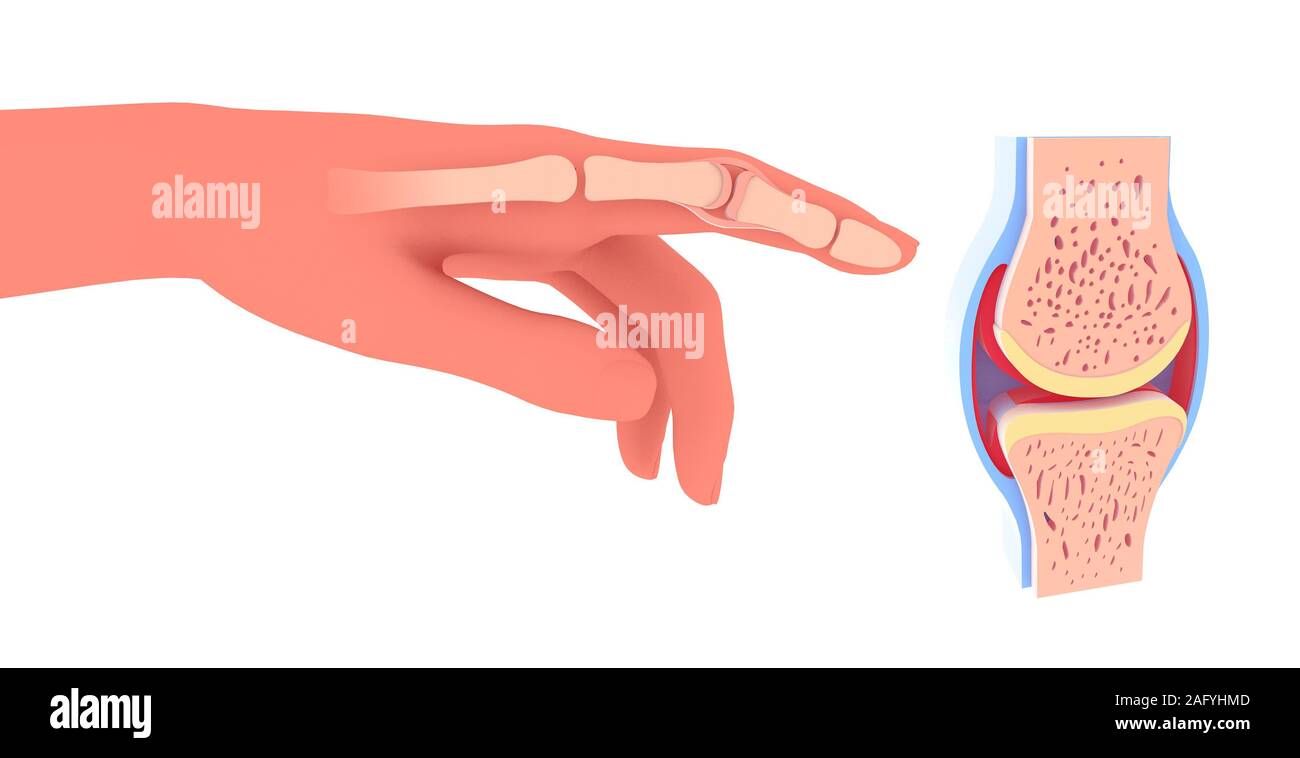

3d illustration of synovial joint. Next to the graphic representation of a hand placing the joint. Stock Photohttps://www.alamy.com/image-license-details/?v=1https://www.alamy.com/3d-illustration-of-synovial-joint-next-to-the-graphic-representation-of-a-hand-placing-the-joint-image336823437.html

3d illustration of synovial joint. Next to the graphic representation of a hand placing the joint. Stock Photohttps://www.alamy.com/image-license-details/?v=1https://www.alamy.com/3d-illustration-of-synovial-joint-next-to-the-graphic-representation-of-a-hand-placing-the-joint-image336823437.htmlRF2AFYHMD–3d illustration of synovial joint. Next to the graphic representation of a hand placing the joint.